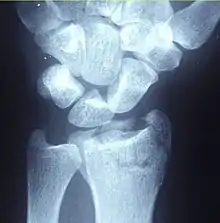

A Colles fracture as seen on X-ray: It is a type of distal radius fracture.

A distal radius fracture, also known as wrist fracture, is a break of the part of the radius bone which is close to the wrist.[1] Symptoms include pain, bruising, and rapid-onset swelling.[1] The ulna bone may also be broken.[1]

In younger people, these fractures typically occur during sports or a motor vehicle collision.[2] In older people, the most common cause is falling on an outstretched hand.[2] Specific types include Colles, Smith, Barton, and Chauffeur's fractures.[2] The diagnosis is generally suspected based on symptoms and confirmed with X-rays.[1]

Diagnosis may be evident clinically when the distal radius is deformed, but should be confirmed by X-ray. The differential diagnosis includes scaphoid fractures and wrist dislocations, which can also co-exist with a distal radius fracture. Occasionally, fractures may not be seen on X-rays immediately after the injury. Delayed X-rays, X-ray computed tomography (CT scan), or Magnetic resonance imaging (MRI) can confirm the diagnosis.